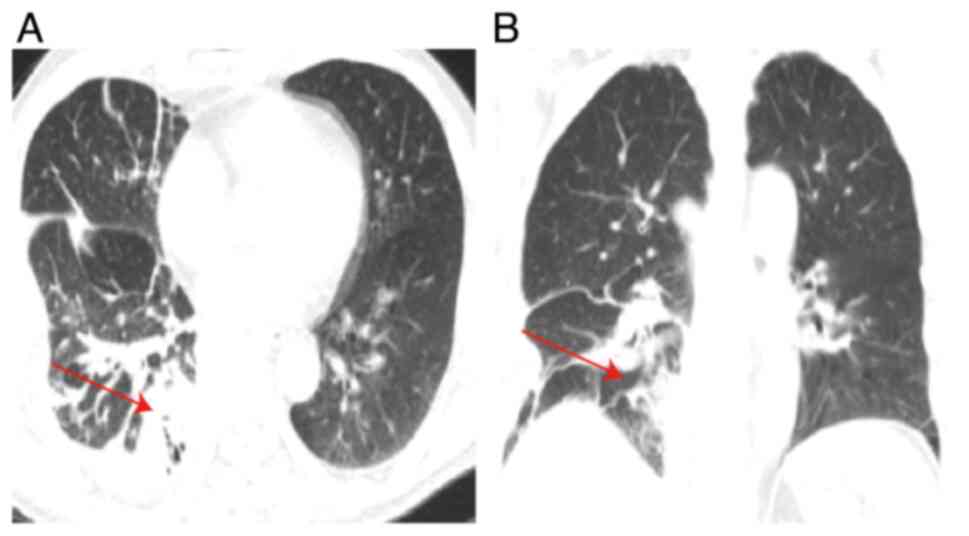

In clinical practice, the management of a lung abscess (LA) usually initiates with antibiotic administration to address the infection. Nevertheless, for cases presenting with refractory pulmonary tumors complicated by a LA, surgical intervention stands as an essential therapeutic recourse. The current study presents case involving lung cancer complicated by a LA. Despite continuously elevated infection marker levels, surgical intervention was promptly performed following the normalization of the patient's temperature. Subsequent postoperative histopathological analysis and immunohistochemistry revealed a moderately differentiated squamous cell carcinoma located in the lower right lung, classified as T2aN0M0, Ib stage. Following a 2‑year follow‑up period, no cancer recurrence was observed and the patient exhibited a favorable prognosis. This case highlights the vital role of surgical timing in the management of lung cancer complicated by an acute LA. Early surgical intervention may play a crucial role in arresting the advancement of lung cancer, indicating that prompt surgery upon temperature normalization could serve as a significant treatment indication for these patients.

Figure 2